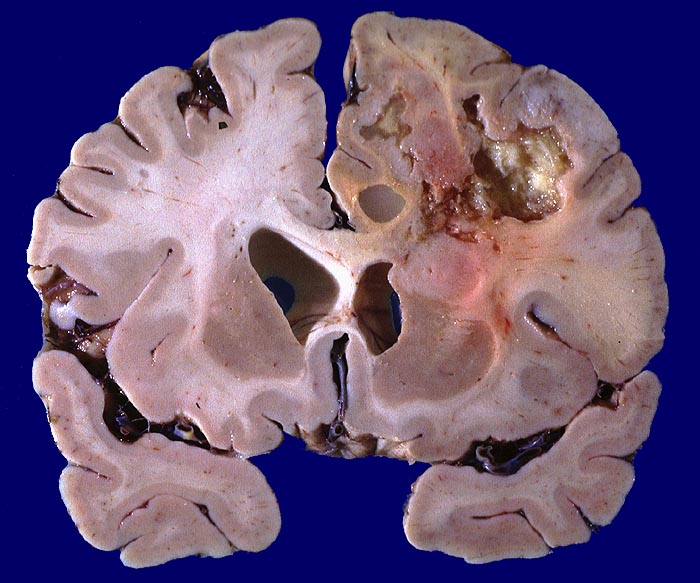

Glioblastoma multiforme

Hirn parietal

Bunte Tumorschnittfläche im parietalen Marklager mit ausgedehnten teils zystischen Nekrosen und unscharfer Begrenzung.

Frontoparietal zystische Nekrosehöhle Durchmesser 6cm. Infiltration von Nc. caudatus, Corpus callosum und Capsula interna rechts.

Hirntumor bekannt seit einem Jahr

Makroskopie